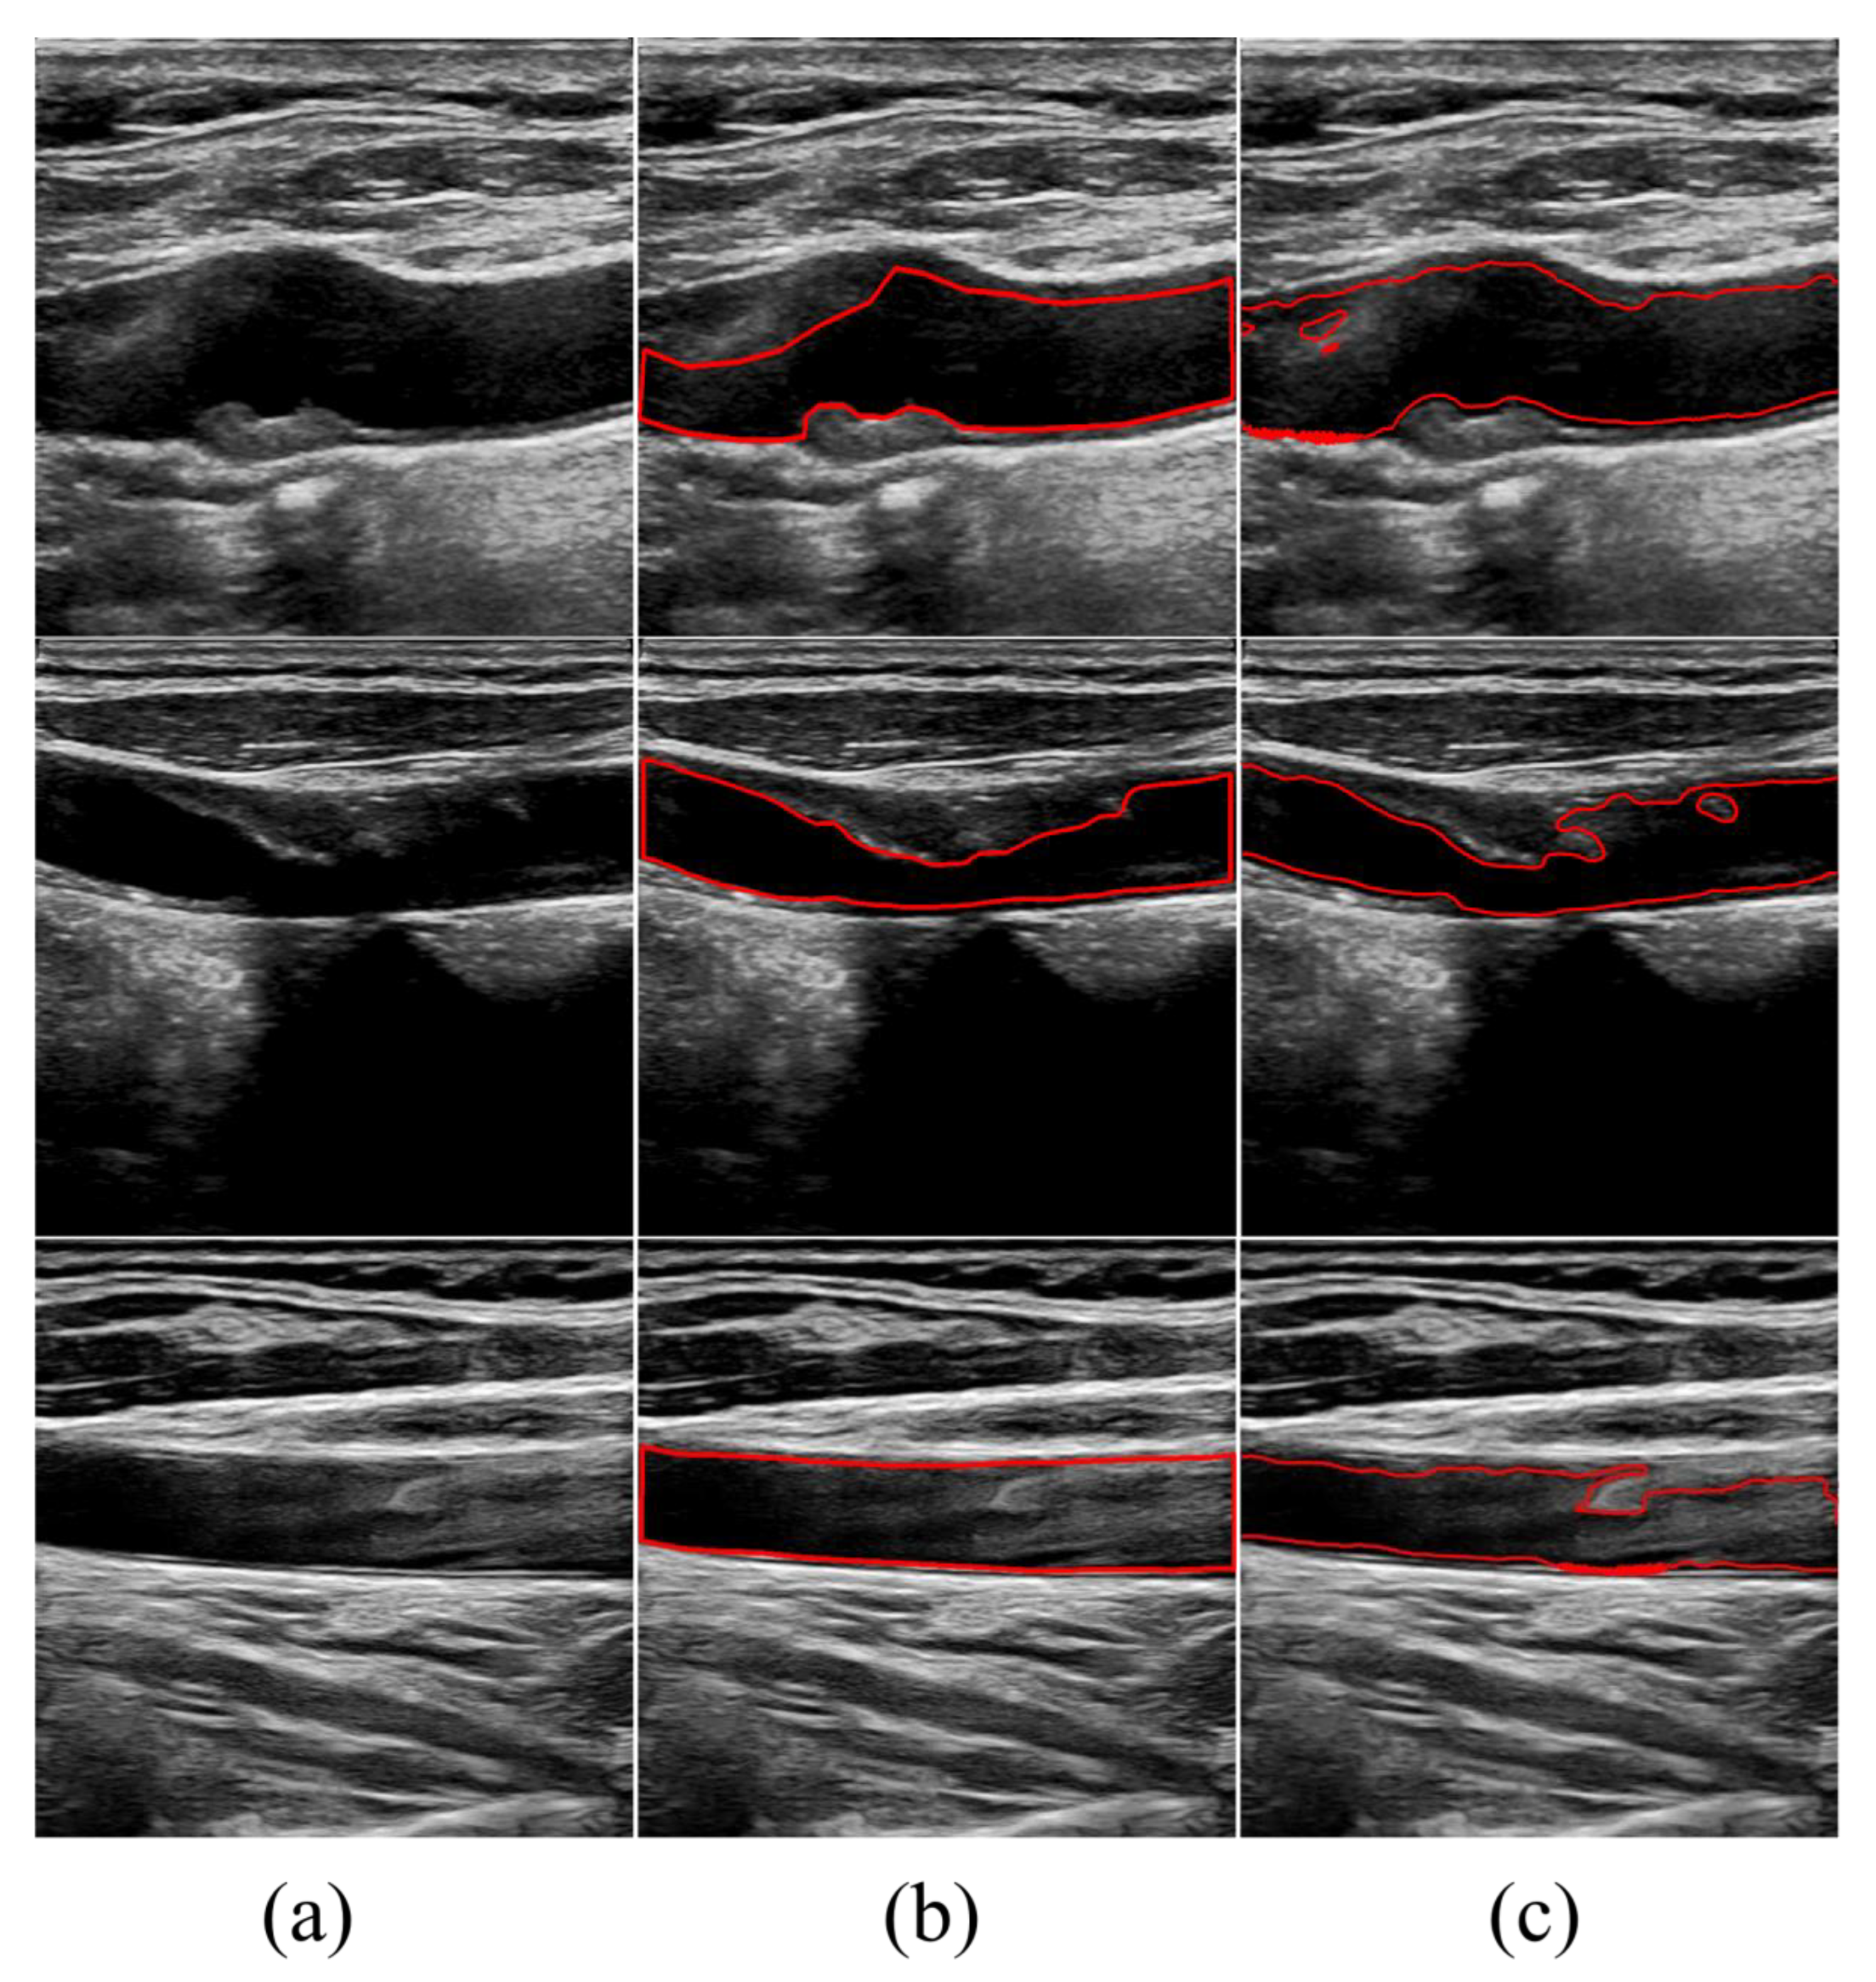

3.4. Experimental Results